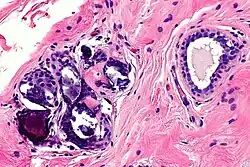

Benign calcification in breast, at high magnification

In most cases, calcification and cysts are the biggest threat of breast augmentation surgery. Fat stem cells that fail to pick up a new blood supply will die and be removed from the body by immune cells. However, if they are missed, the cluster will lead to calcification and cyst formation. These are visible on the breast as lump sometimes and are more dangerous when these dead cells are detected as cancer cells, which hinders an accurate diagnosis of breast cancer. The calcified tissue will be diagnosed as a benign cancer and not cause any harm. However, if the tissue is severely damaged the entire breast needs to be removed. Once a patient is diagnosed with breast implant calcification, regular mammograms should be done to monitor the possible cancer development.[16]